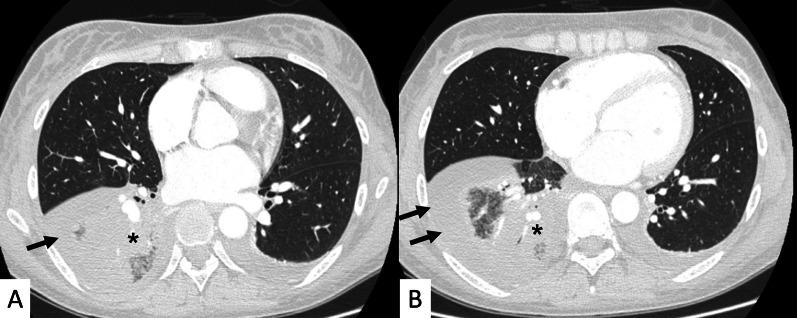

Connective tissue diseases (CTDs) include a spectrum of disorders that affect the connective tissue of the human body; they include autoimmune disorders characterized by immune-mediated chronic inflammation and the development of fibrosis. Lung involvement can be misdiagnosed, since pulmonary alterations preceded osteo-articular manifestations only in 20% of cases and they have no clear clinical findings in the early phases. All pulmonary structures may be interested: pulmonary interstitium, airways, pleura and respiratory muscles. Among these autoimmune disorders, rheumatoid arthritis (RA) is characterized by usual interstitial pneumonia (UIP), pulmonary nodules and airway disease with air-trapping, whereas non-specific interstitial pneumonia (NSIP), pulmonary hypertension and esophageal dilatation are frequently revealed in systemic sclerosis (SSc). NSIP and organizing pneumonia (OP) may be found in patients having polymyositis (PM) and dermatomyositis (DM); in some cases, perilobular consolidations and reverse halo-sign areas may be observed. Systemic lupus erythematosus (SLE) is characterized by serositis, acute lupus pneumonitis and alveolar hemorrhage. In the Sjögren syndrome (SS), the most frequent pattern encountered on HRCT images is represented by NSIP; UIP and lymphocytic interstitial pneumonia (LIP) are reported with a lower frequency. Finally, fibrotic NSIP may be the interstitial disease observed in patients having mixed connective tissue diseases (MCTD). This pictorial review therefore aims to provide clinical features and imaging findings associated with autoimmune CTDs, in order to help radiologists, pneumologists and rheumatologists in their diagnoses and management.

结缔组织病(CTDs)包括一系列影响人体结缔组织的疾病;它们包括以免疫介导的慢性炎症和纤维化发展为特征的自身免疫性疾病。肺部受累可能会被误诊,因为肺部改变仅在20%的病例中先于骨关节炎表现出现,且在早期阶段没有明确的临床发现。所有肺部结构都可能受累:肺间质、气道、胸膜和呼吸肌。在这些自身免疫性疾病中,类风湿关节炎(RA)的特征是普通型间质性肺炎(UIP)、肺结节和伴有空气潴留的气道疾病,而系统性硬化症(SSc)常表现为非特异性间质性肺炎(NSIP)、肺动脉高压和食管扩张。NSIP和机化性肺炎(OP)可见于多发性肌炎(PM)和皮肌炎(DM)患者;在某些情况下,可观察到小叶周围实变和反晕征区域。系统性红斑狼疮(SLE)的特征是浆膜炎、急性狼疮性肺炎和肺泡出血。在干燥综合征(SS)中,HRCT图像上最常见的表现是NSIP;UIP和淋巴细胞间质性肺炎(LIP)的报道频率较低。最后,纤维化NSIP可能是混合性结缔组织病(MCTD)患者中观察到的间质性疾病。因此,本图像综述旨在提供与自身免疫性CTDs相关的临床特征和影像学表现,以帮助放射科医生、呼吸科医生和风湿病科医生进行诊断和管理。